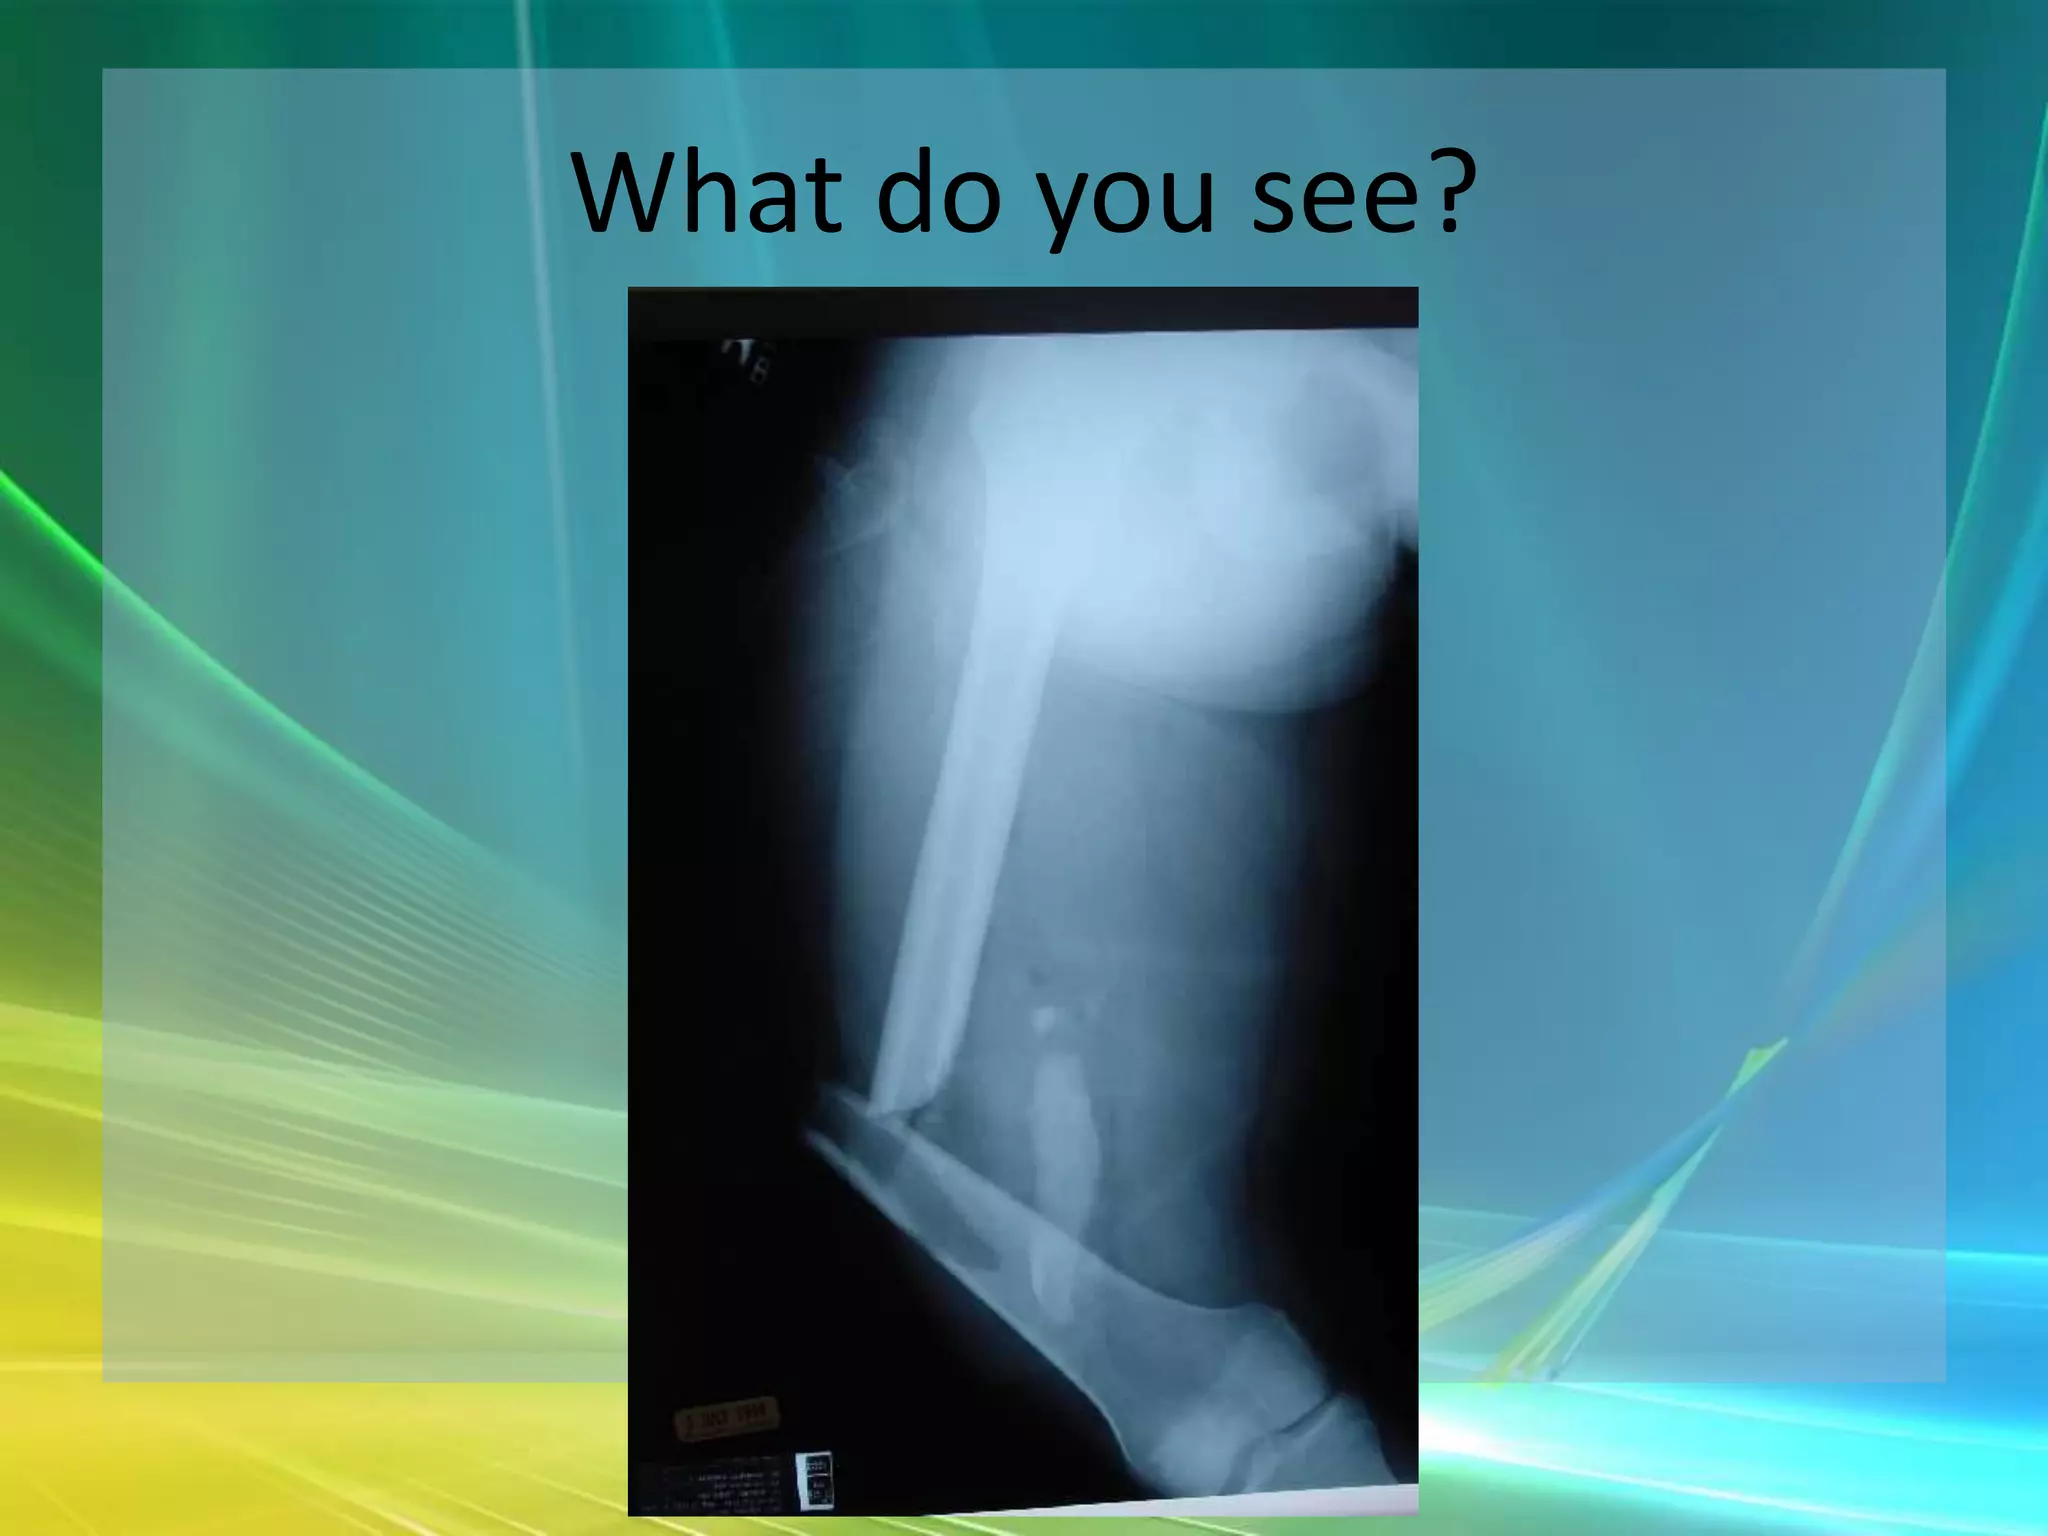

What do you see?